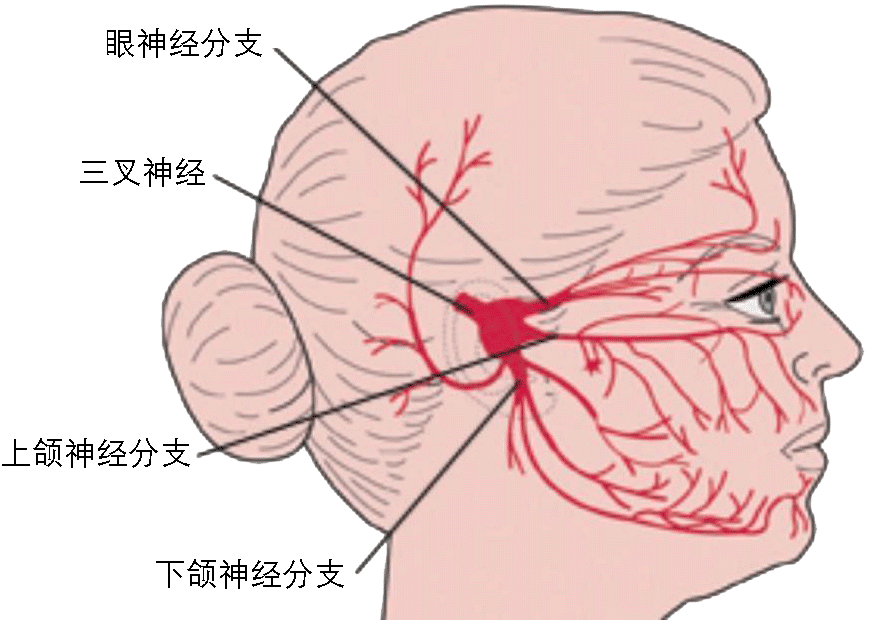

三叉神经分布区内反复发作的阵发性、短暂、剧烈疼痛而不伴三叉神经功能破坏的症状,称三叉神经痛。常于40岁后起病,女性较多。

病因:原发性三叉神经痛的病因尚未明确。目前认为三叉神经在脑桥被异行扭曲的血管压迫三叉神经后根,局部产生脱髓鞘变化而导致疼痛发作。

临床表现:三叉神经痛为骤然发生的剧烈疼痛,但严格限于三叉神经感觉支配区内。发作时患者常紧按患侧面部或用力擦面部减轻疼痛,可致局部皮肤粗糙,眉毛脱落。有的发作时不断做咀嚼动作,严重者可伴有同侧面部肌肉的反射性抽搐,所以又称“痛性抽搐”。

治疗:继发性三叉神经痛者应针对病因治疗。原发性三叉神经痛目前还缺乏绝对有效的治疗方法,治疗原则以止痛为目的,药物治疗为主,无效时可用神经阻滞疗法或手术治疗。主要的手术治疗方法有:微血管减压术、三叉神经切断术。

微血管减压术:用涤纶片隔离三叉神经与邻近血管。

三叉神经切断术